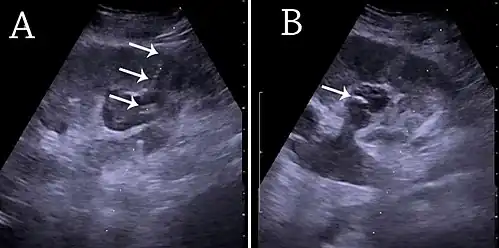

(A) Ультразвуковое исследование трубки почечной чрескожной нефростомы, расположенной в чашечке в нижнем полюсе почки с гидронефрозом. (B) Катетер помещают в расширенную чашечку. Трубка в (A) и катетер в (B) отмечены белыми стрелками.